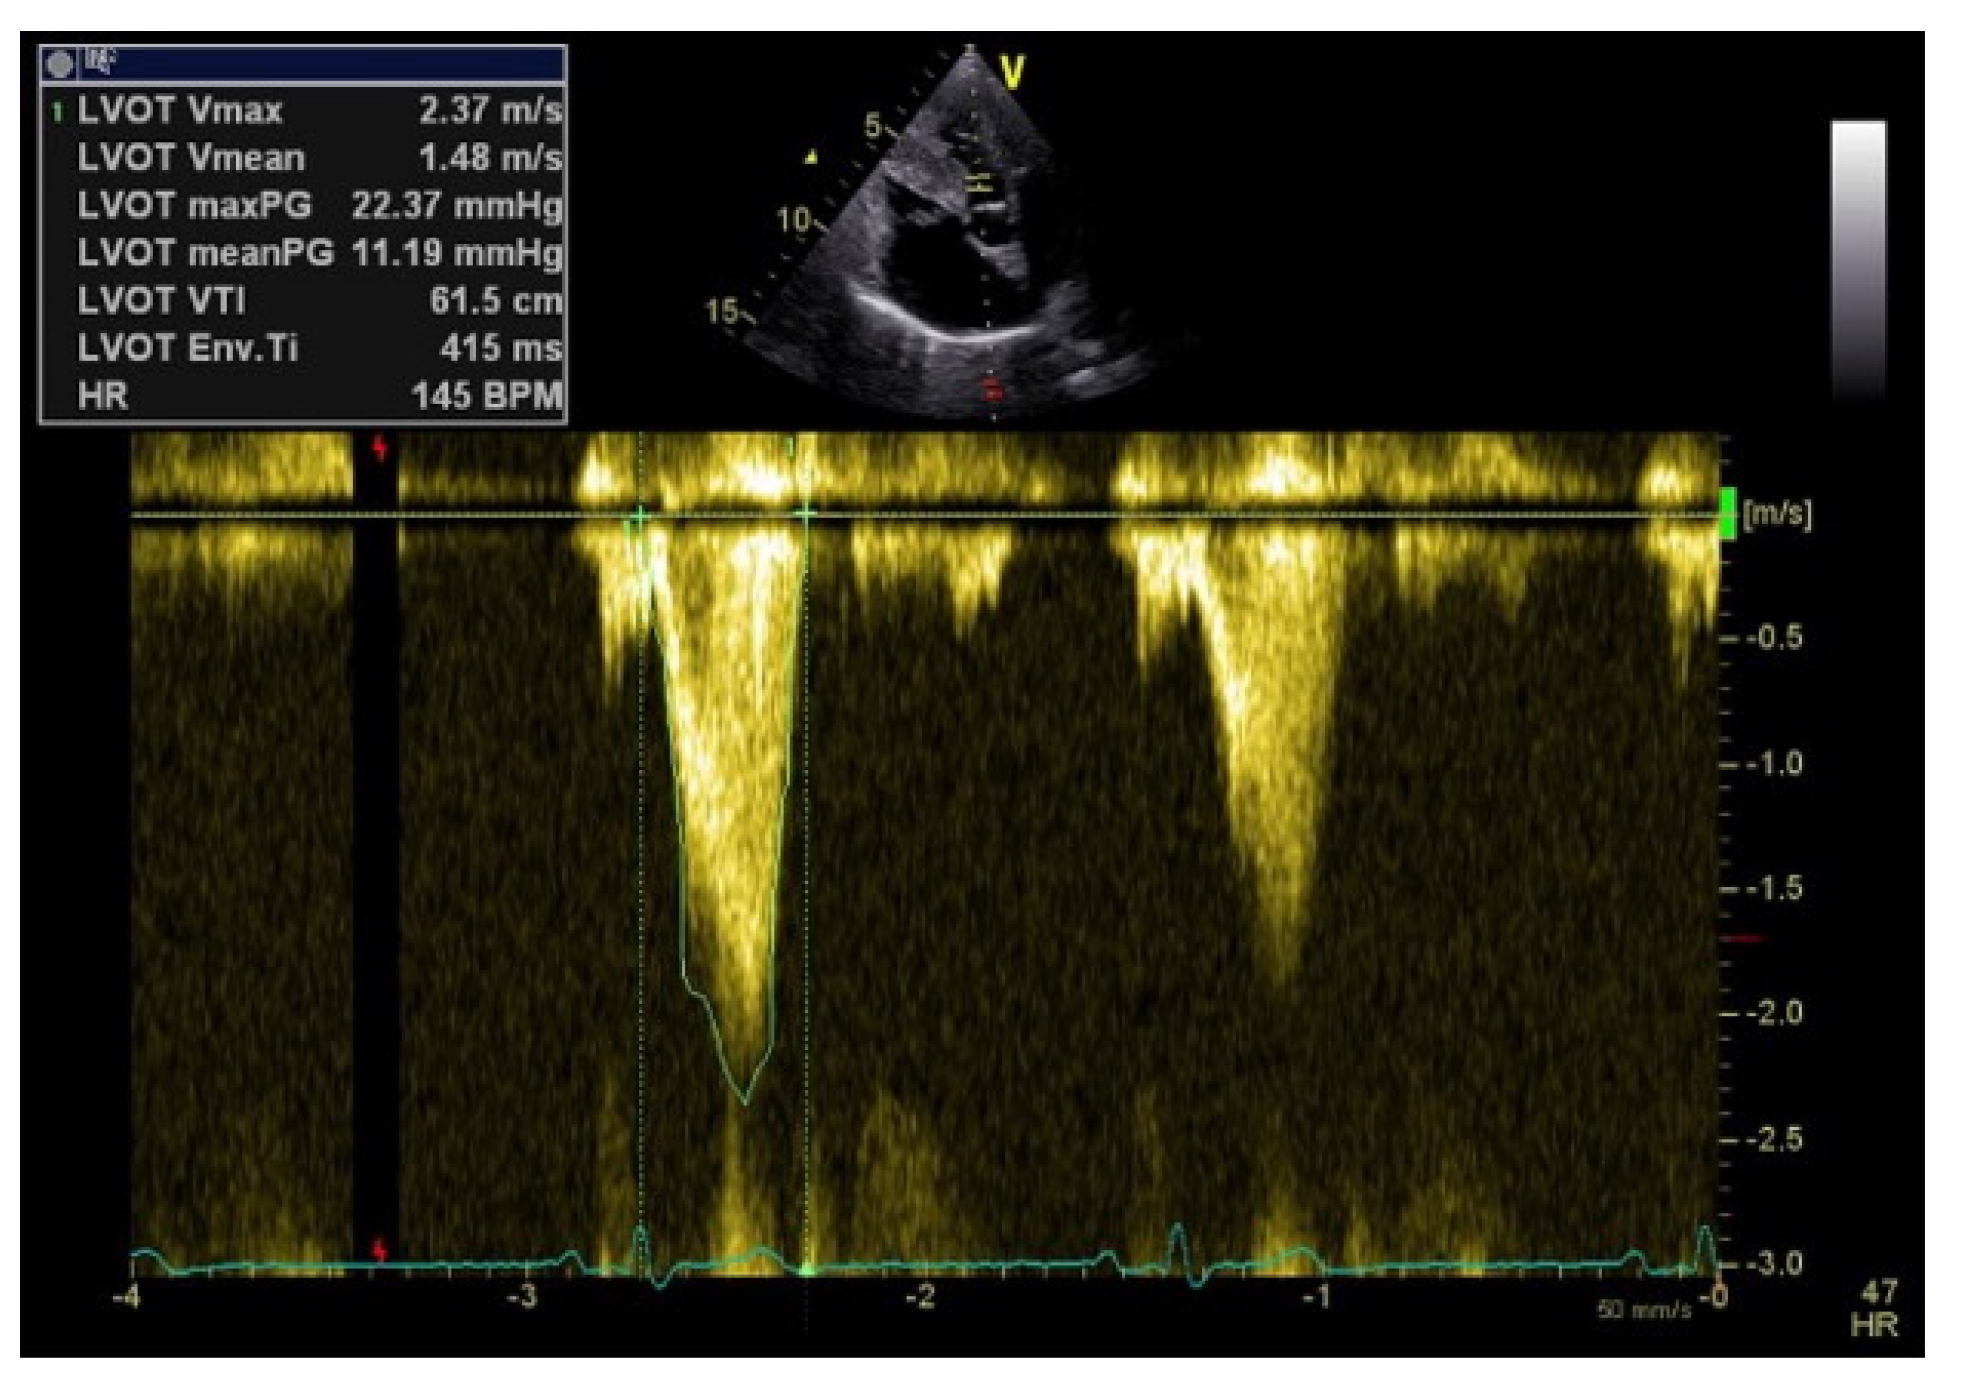

| Perfusion parameters | LVOT VTI and CI | A reliable quantitative parameter that truly reflects circulatory status and global end organ perfusion | LVOT VTI ≥ 18 cm CI ≥ 2.5 L/min/m2 |

| LVOTO | Its diagnosis leads to drastic changes in the clinical management | LVOTO < 30 mmHg | |